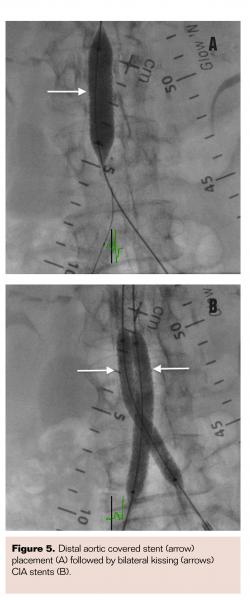

An Ocelot catheter (Avinger) was advanced from the right CFA to cross the chronic total occlusion (CTO) in the CIA (Figure 3A) with optical coherence tomography (OCT) imaging (Figure 3B) to allow direct visualization during crossing and to maintain intraluminal position. Although the catheter maintained this position up to the aortoiliac bifurcation, it entered into a subintimal plane in the distal aorta due to heavy distal calcifications despite multiple attempts to maneuver the catheter within the lumen. A Grand Slam guidewire (Abbott Vascular) was maintained in this position in the subintimal plane from the right femoral access. The same steps were then performed from the left CFA to wire the subintimal plane in the distal aorta and another Grand Slam guidewire maintained in this position from the left femoral access. A Pioneer Plus re-entry catheter (Volcano Corporation) was then advanced over the Grand Slam wire from the right-sided access (Figure 4A) to re-enter the true lumen of the aorta with intravascular ultrasound (IVUS) guidance (Figure 4B), allowing the re-entry wire to advance into the proximal descending aorta. The same technique was then repeated from the left-sided access to maintain a guidewire in the proximal descending aorta. Simultaneous balloon angioplasty was performed of the reentry site with two 6 x 40 mm Sterling balloons (Boston Scientific). A single iCAST 10 mm x 38 mm balloon-expandable covered stent (Maquet) was deployed as a distal aortic cuff in the infrarenal position (Figure 5A). Two iCAST 7 mm x 59 mm covered stents were then simultaneously deployed to extend from within the initial aortic cuff stent into the bilateral CIAs (Figure 5B). Two additional iCAST 7 mm x 59 mm stents were then deployed in bilateral CIAs to cover the entire occluded segment. Final aortogram from the left radial artery access site confirmed patent aortic stents with bilateral limb extensions with brisk flow (Figure 6). Both internal iliac arteries were noted to be patent. Hemostasis was achieved in bilateral femoral access sites via manual compression upon normalization of activated clotting time.